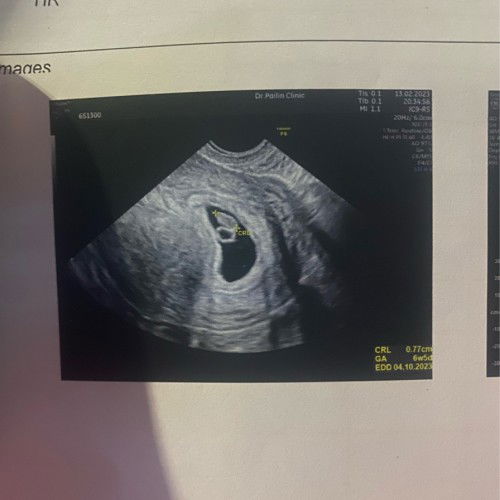

6w5dตอนนี้กังวลมากเลยค่ะ เคียด

6w5d ก่อนหน้านี้หมอเคยบอกว่าอยู่ในช่วงระยะแท้งคุกคามกัอกินยาตามที่หมอให้ก็ดีขึ้นน่ะค่ะเลือดก้อหยุดไป แต่ตอนนี้กังวลมากเลยค่ะ มีเลือดสีสดออกหลังจากฉี่เสร็จ คือเวลาใช้กระดาษเช็ดชูเช็ดจะมีเลือดติดมาด้วยตลอดเลยค่ะ